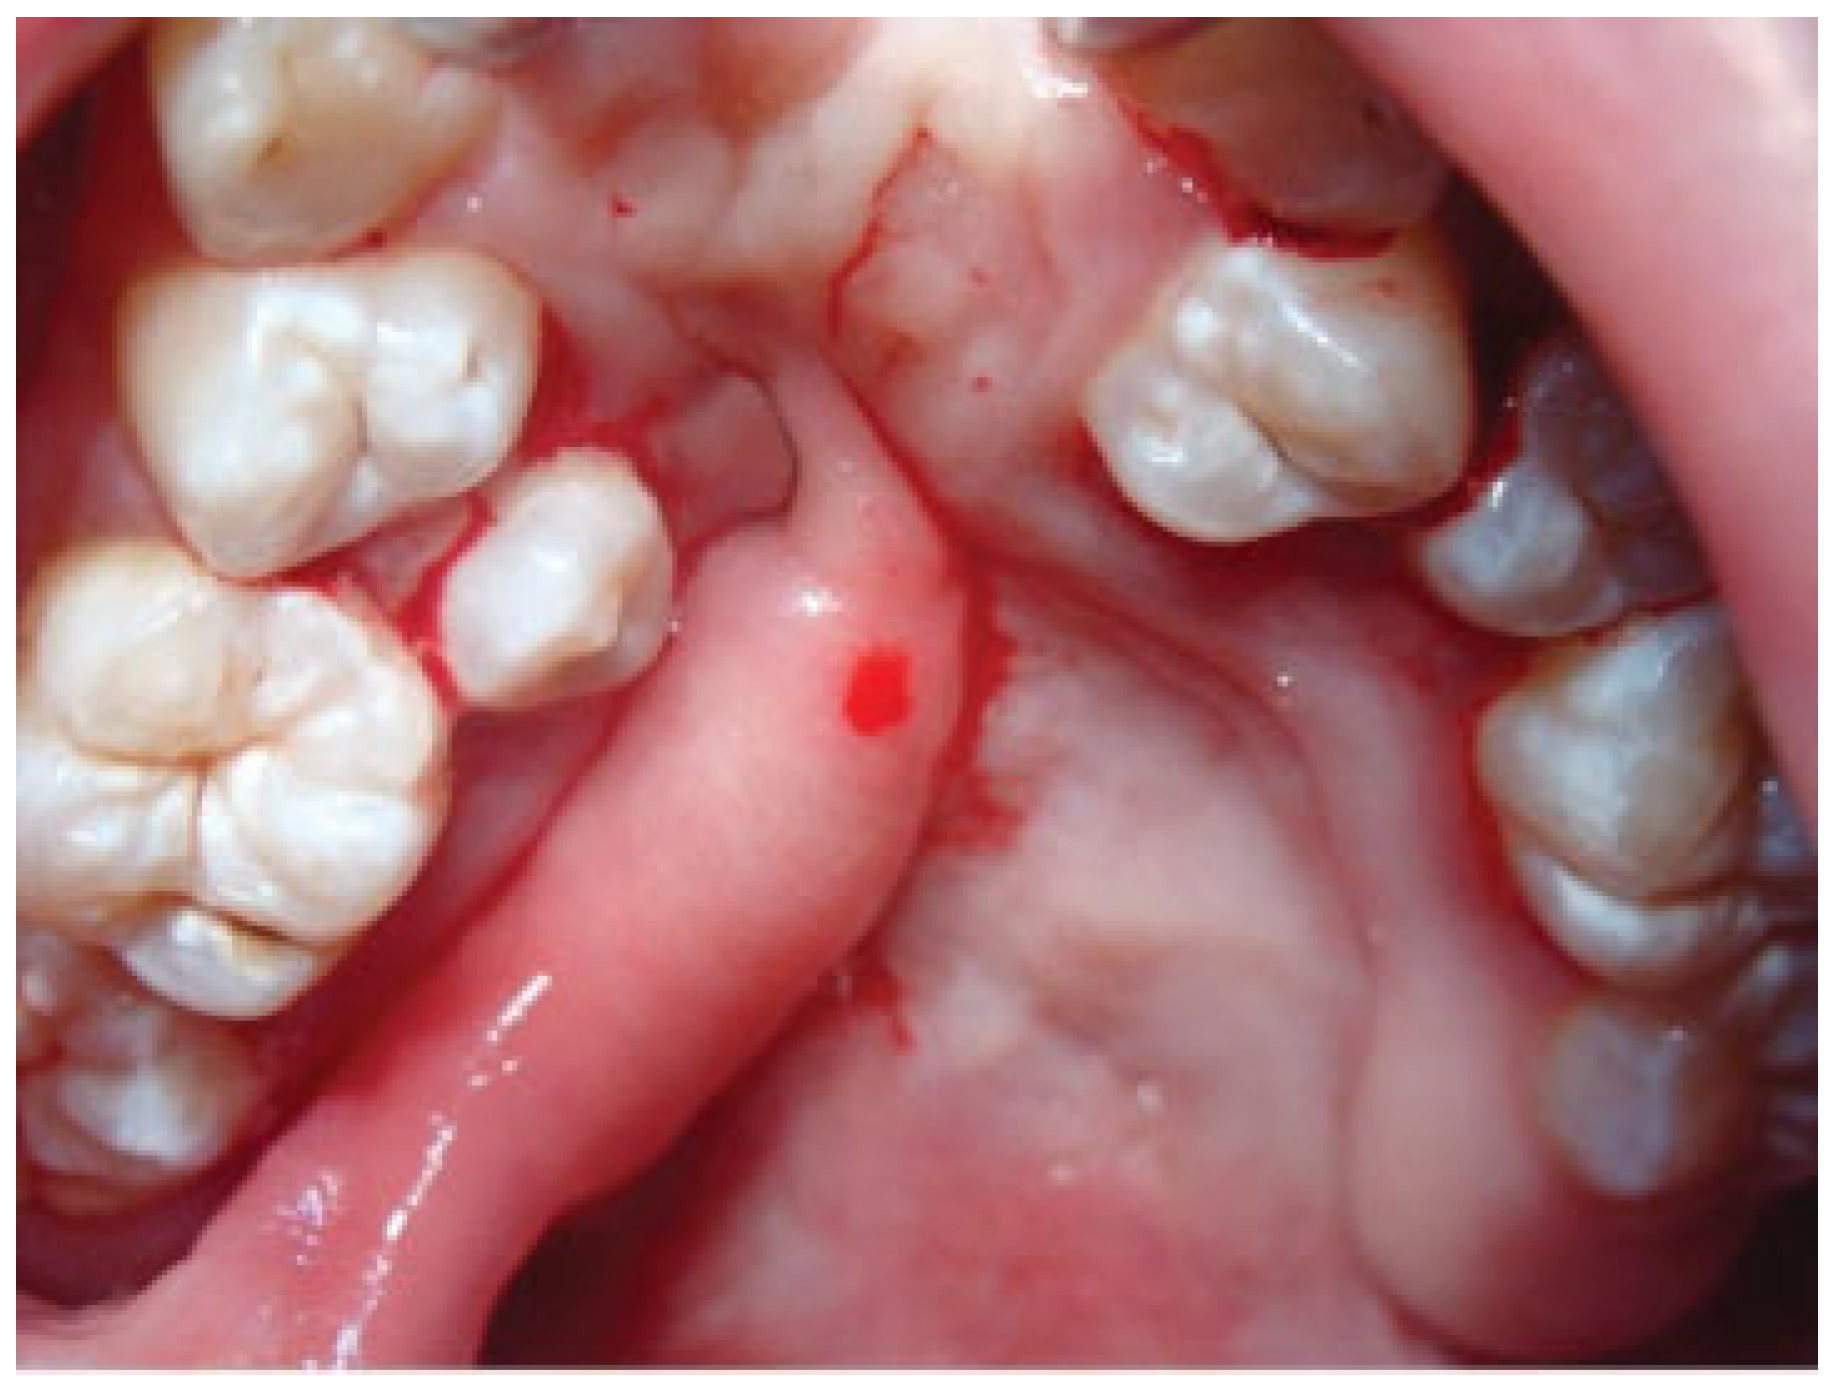

Palatal fistula is a difficult complication after cleft palate repair. The repair of a palatal fistula can be challenging, particularly in wide and recurrent fistulas (Figure 1). Large defects after cleft palate repair produce various symptoms, including regurgitation of fluid into the nasal cavity, hearing loss, and velopharyngeal insufficiency. In these cases, the palatal tissue around the fistula can be quite scarred and in short supply. A variety of reconstructive options are commonly employed, using local flaps of muscle and mucosa or tongue tissue or using distant flaps [1,2,3]. The combination of buccal mucosal flaps and buccinator muscle as an axial myomucosal flap based on the facial artery has been described by Pribaz et al. [2].

Figure 1. Severe palatal fistula after primary palatoplasty in a 7-year-old patient.